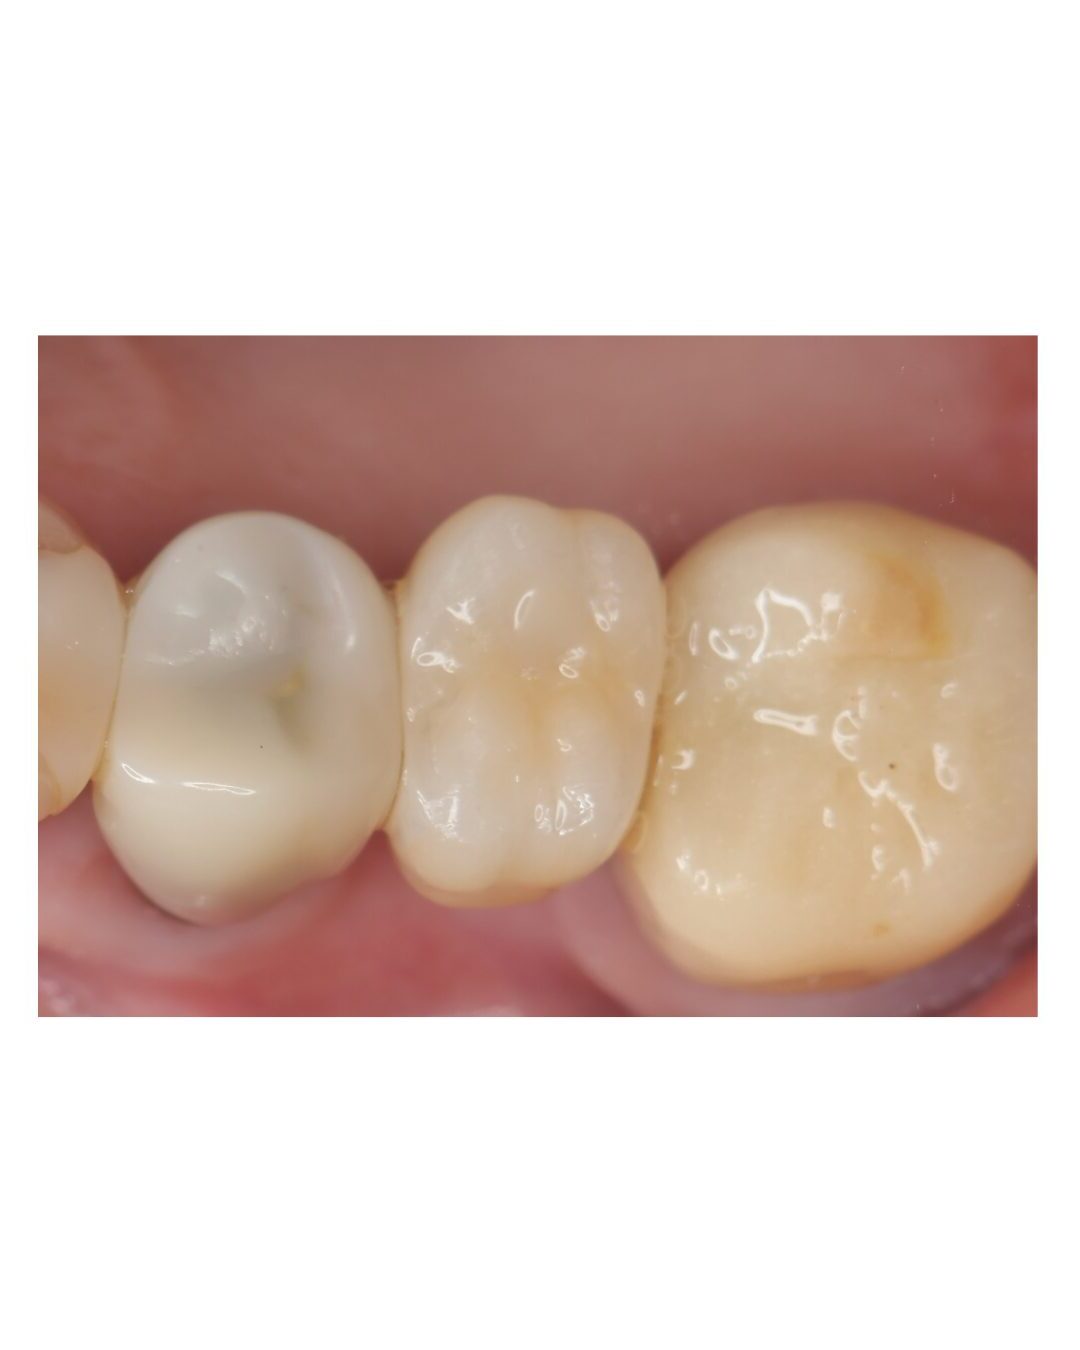

③ 最終補綴|セラミッククラウンを装着

骨結合の安定を確認した後、最終的にセラミッククラウンを装着しました。

噛む機能と自然な見た目を回復し、清掃性にも配慮した形態にしています。

治療後も、長く良い状態を保つためには、噛み合わせの確認と定期メンテナンスが重要です。

術前後の比較|欠損部に固定式の歯が入り、噛みやすい状態へ

治療前は上顎奥歯が欠損しており、咀嚼効率の低下や噛み合わせの偏りが懸念される状態でした。

治療後は固定式の被せ物が入り、奥歯で噛む機能の回復を目指せる状態になりました。